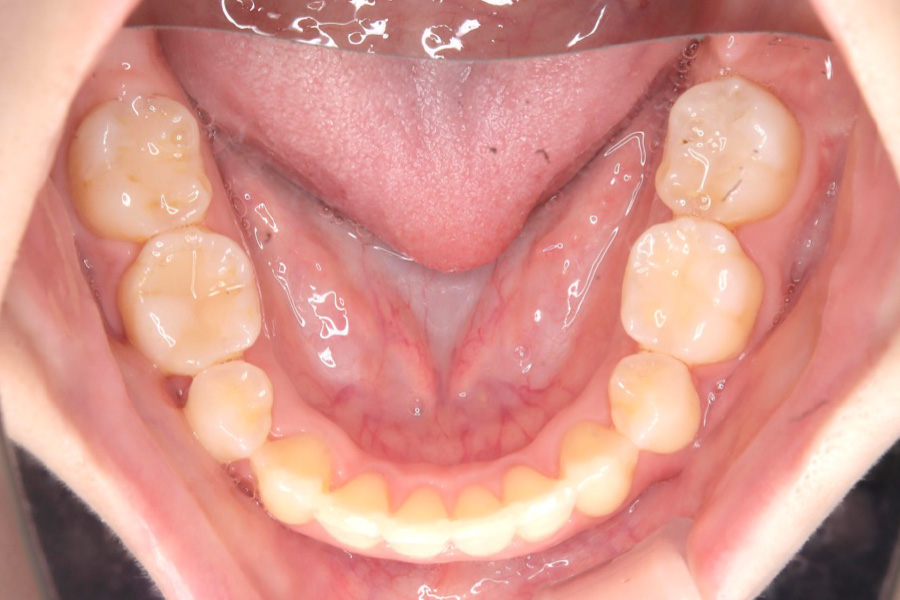

【20代女性】

全体のガタつきを

インビザライン矯正で治療したケース

治療前

主訴 全体のガタつきが気になる

治療内容 インビザライン矯正

小臼歯抜歯